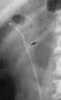

Ureteral stent

A ureteral stent (pronounced you-REE-ter-ul), or ureteric stent, is a thin tube inserted into the ureter to prevent or treat obstruction of the urine flow from the kidney. The length of the stents used in adult patients varies between 24 and 30 cm. [Source: Wikipedia ]